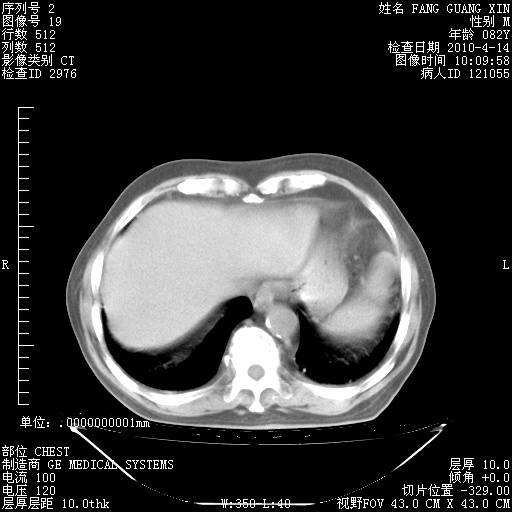

肺部CT平扫未见异常。

4月14日肺部CT